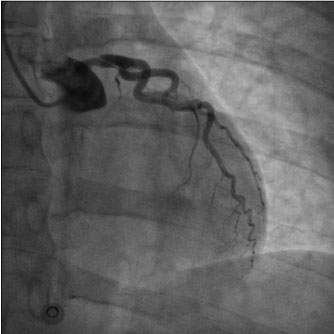

Physical examination did not add pathological details. Respiratory rate was 16/min. Normal S1 and S2 heart sounds were present, no murmurs or gallops were detected. There were no signs of heart failure visible. The pain was constant, independent from both decubitus and respiratory movements. Measured arterial pressure was 95/70 mmHg, while peripheral oxygen saturation was 95%. EKG revealed sinus rhythm at 75 bpm, normal AV conduction, 1 mm ST downslope in D2-D3-aVF and V4V5-V6, 1 mm ST elevation in aVR and 1.5 mm in V1-V2, delayed R-wave progression from V1 to V4 (Figure 1). Suspecting an acute coronary syndrome (ACS) or an acute aortic disease, our Cath Lab (about one hour’s drive distant) was contacted and the transfer was activated. General treatment measures were initiated: Lysine Acetylsalicylate 500 mg e.v., intravenous infusion of sodium chloride solution and proton pump inhibitor e.v. During the transfer to our hospital, arterial pressure persisted on low thresholds, while chest pain maintained the same characteristics with lower intensity. Emergent coronary angiography through radial approach was performed at the arrival in our hospital, and it showed TYPE 1 left main coronary dissection with TIMI 2 flow in left anterior descending coronary artery and left circumflex artery, while no angiographically significant stenosis were detected. Right coronary artery showed good canalization (Figure 2). EKG pattern presented a partial improvement at the end of the procedure. In light of the angiographical result and the hemodynamical instability, considering that arterial pressure gradually decreased reaching values below 85/60 mmHg, we opted for positioning an intra-aortic balloon pump (IABP) 1:1 through right femoral access, sending then the patient to surgical revascularization. Pre-operative blood gas analysis showed pH 7.39, pO2 177.5 mmHg with FiO2 50%, pCO2 32.6 mmHg, HCO3- 20 mmol/L, Lactates 0.59 mmol/L, K+ 3.3 mmol/L. In the operating room, a pre-surgical trans-oesophageal echocardiography was performed and it revealed a global left ventricle hypokinesis with marked hypo-akinesis of interventricular septum. The patient underwent on-pump double coronary artery bypass grafting (CABG) with anastomosis between internal mammary artery and left anterior descending coronary and between saphenous graft and obtuse marginal branch. After the surgery hemodynamics was supported with IABP 1:1, Adrenaline 0.2 micrograms/kg/min and Noradrenaline 0.1 micrograms/kg/min infusion, Levosimendan was also administered in a 24 h infusion at 0.05 micrograms/kg/min. Troponin levels measured 8 hours after the procedure were 7027 pg/ml. In addition, Cabergoline 0.25 mg every 12 hours for 48 hours was considered, with the aim to decrease lactation.

Figure 2: Coronary angiography showing spontaneous left main coronary artery dissection. View Figure 2